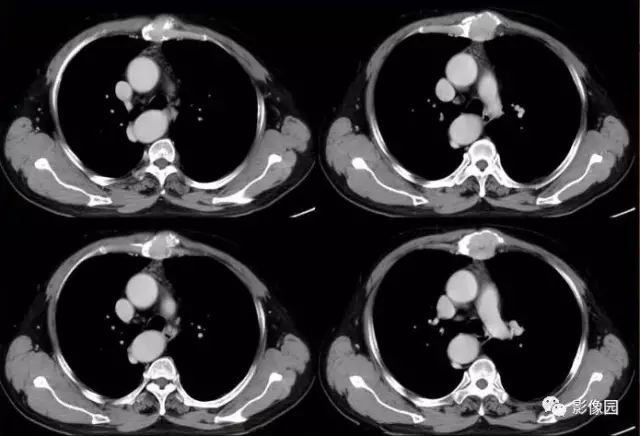

肚肚丫头: 胸骨体局部呈膨胀性骨质吸收破坏,内呈软组织密度影,可见点状钙化,增强扫描呈轻度强化,周围软组织略肿胀。考虑:1.骨巨细胞瘤;2.浆细胞瘤;3.嗜酸性肉芽肿

CT表现:特征性穿凿状、鼠咬状及蜂窝状骨破坏,边缘清楚,骨质疏松,病理性骨折及软组织肿块等表现,骨质硬化及骨膜反应少见。

骨破坏区完全为软组织取代,骨质膨胀,边界清楚,常突破骨皮质形成软组织肿块。增强扫描可见病灶轻中度强化,一般于静脉期达峰值。